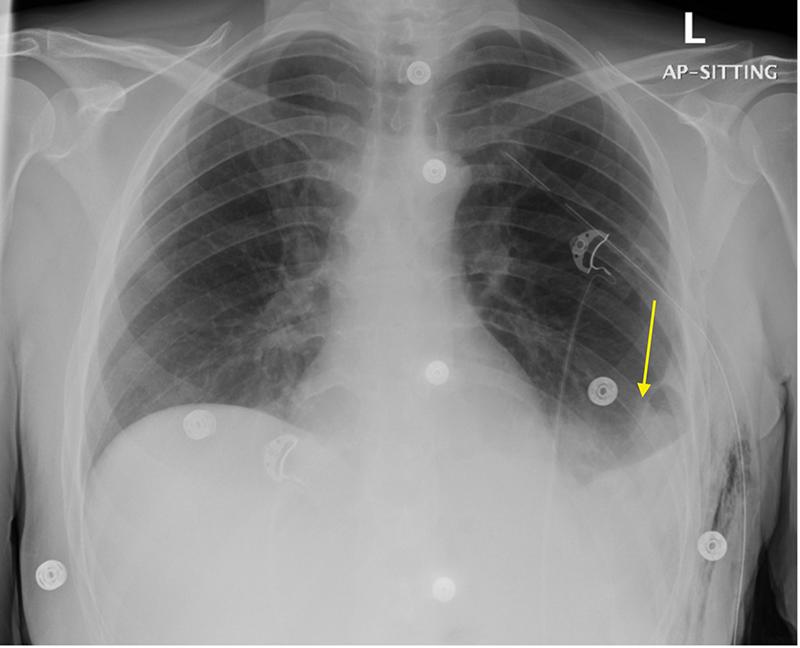

On physical examination, he was hemodynamically stable. His abdomen was soft and non-tender, with no palpable masses. Respiratory examination revealed decreased breath sounds at the left lower lung field. Chest x-ray revealed a large left diaphragmatic hernia with abdominal contents herniating into the left hemithorax, causing mediastinal shift to the right (Figure 1A). Contrast-enhanced CT of the chest, abdomen, and pelvis demonstrated a left posterior diaphragmatic defect measuring approximately 5 × 7 cm, with herniation of small bowel loops, the splenic flexure of the colon, and the left kidney. The left lung volume was reduced with mild ground-glass opacities in the left lower lobe. No evidence of bowel obstruction or ischemia was noted (Figure 1B).

Figure 1. (A) Chest x-ray, AP view. Showing a large left diaphragmatic hernia with abdominal contents in the left hemothorax (arrows), and a mediastinal shift towards the right side. (B) Preoperative CT scan of the chest, abdomen, and pelvis with contrast, coronal view. Showing a left posterior defect on the left hemidiaphragm with herniation of small bowel loops, splenic flexure of the colon and left kidney with a hernia defect measuring about 5 × 7 centimeter (Arrow; splenic flexure of the colon. X; small bowels, *; left kidney).